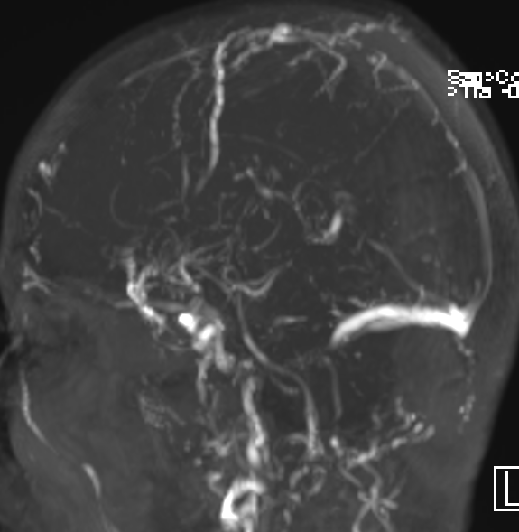

2013-5-16 MRI